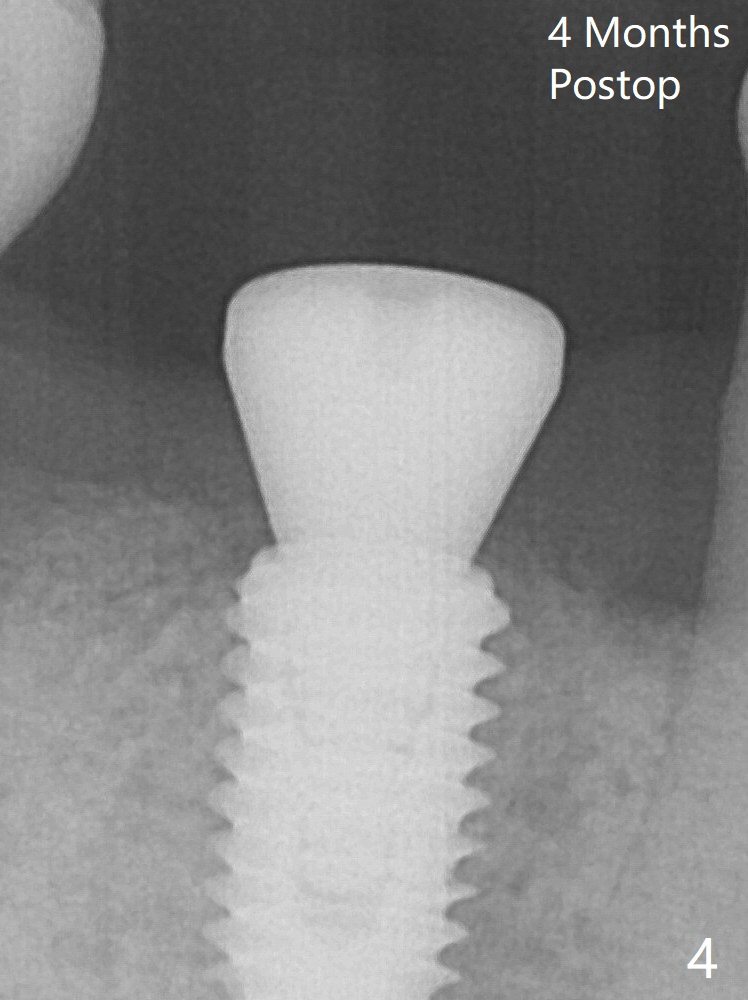

Minimal bone loss is observed 4 months postop (Fig.4 (smoker)).